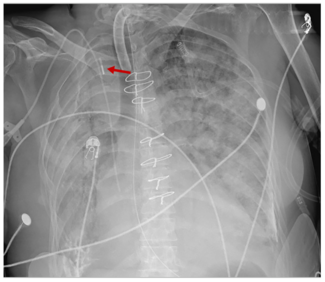

A 55-year-old female with a history of cardiac transplant-related coronary artery vasculopathy, disseminated fungal lung infection, and chronic respiratory failure presented with dyspnea and an increased oxygen requirement. Notable were a...